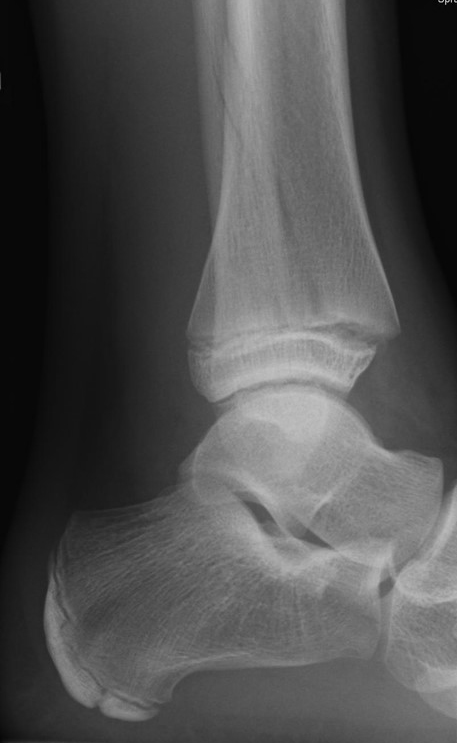

Fugengelenkfrakturen treten typischerweise vor dem 10. Lebensjahr auf, in einer Phase, in welcher die Wachstumsfugen noch weit offen sind. Dieser Frakturtyp betrifft fast ausschließlich den medialen Malleolus. Laterale Frakturen sind extrem selten, teilweise kommt es zu lateralen Bandverletzungen oder Fugenschaftfrakturen der distalen Fibula. Die Frakturlinie verläuft in einer Verlängerungslinie von der medialen Taluskante nach proximal. Häufig stellen sich Verletzungen des Innenknöchels im Röntgenbild schlechter dar, insbesondere wenn die Aufnahmen verdreht sind oder die Ebene der Fraktur bei geringer Dislokation verkippt zur Röntgenebene liegt. Besteht klinisch der geringste Hinweis auf eine Verletzung des Innenknöchels, muss aufgrund der Tragweite der Verletzung durch entsprechende Aufnahmen gegebenenfalls auch Schnittbildverfahren die Verletzung sicher diagnostiziert oder ausgeschlossen werden (Abb. 15).